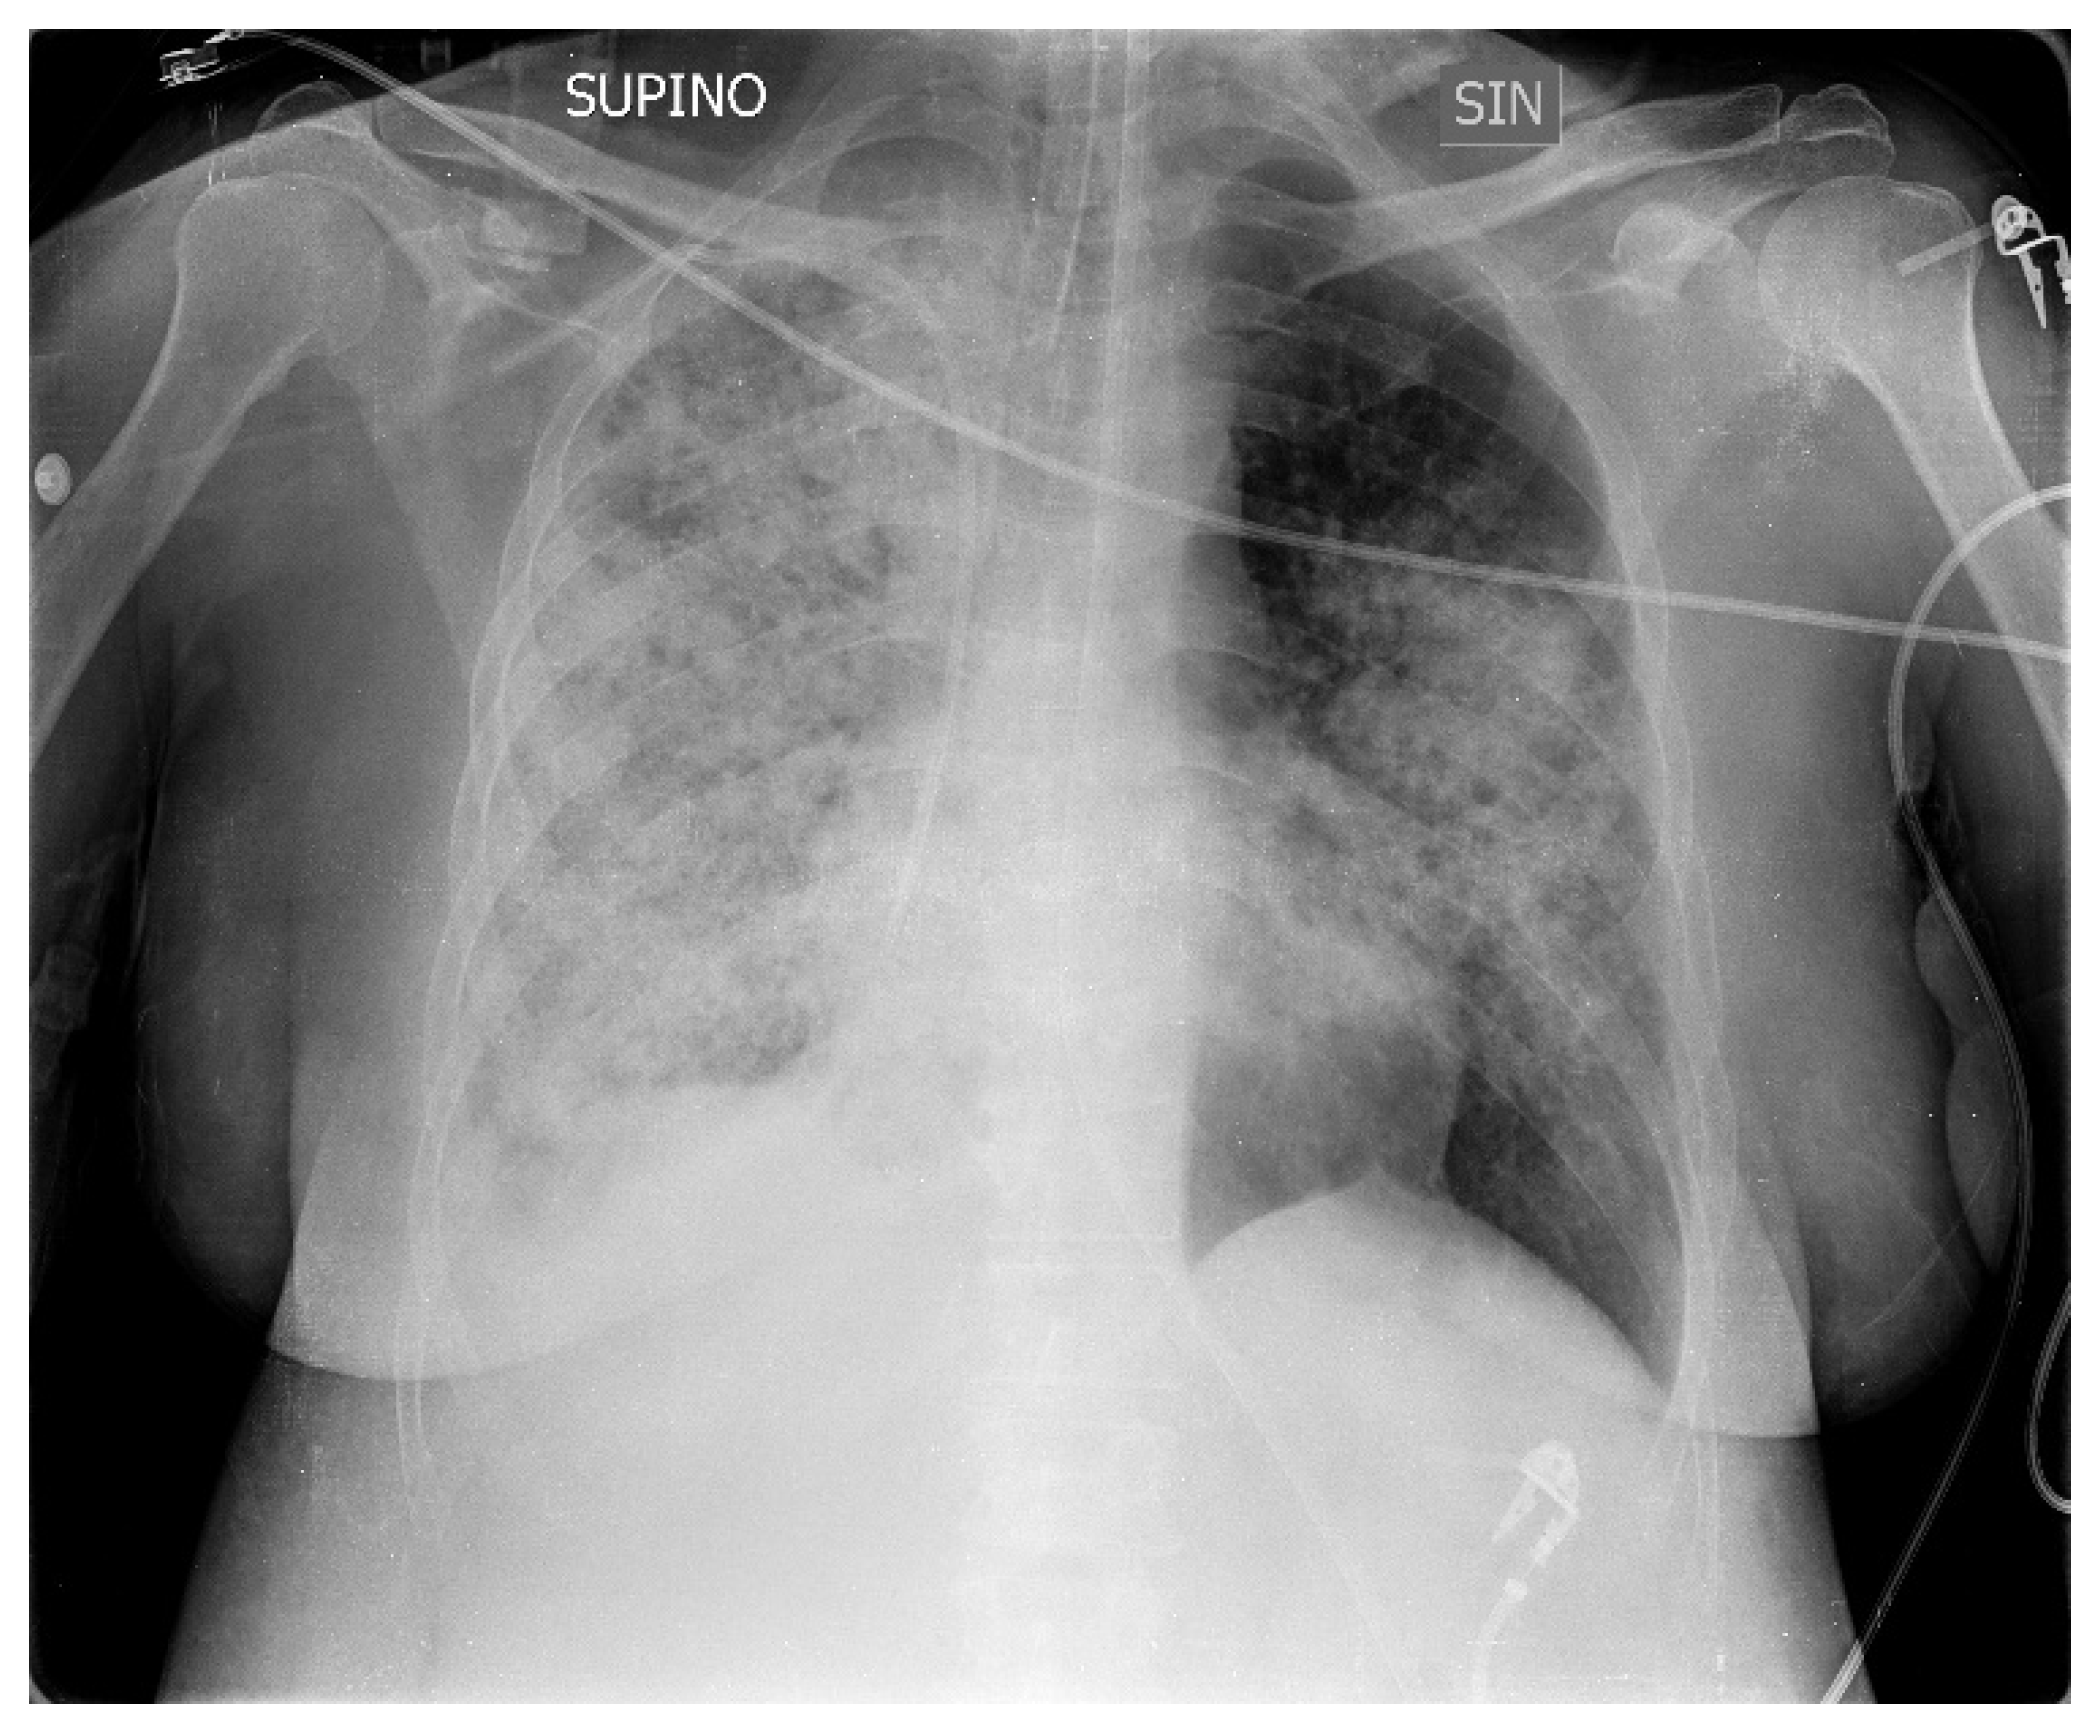

2. Case Presentation